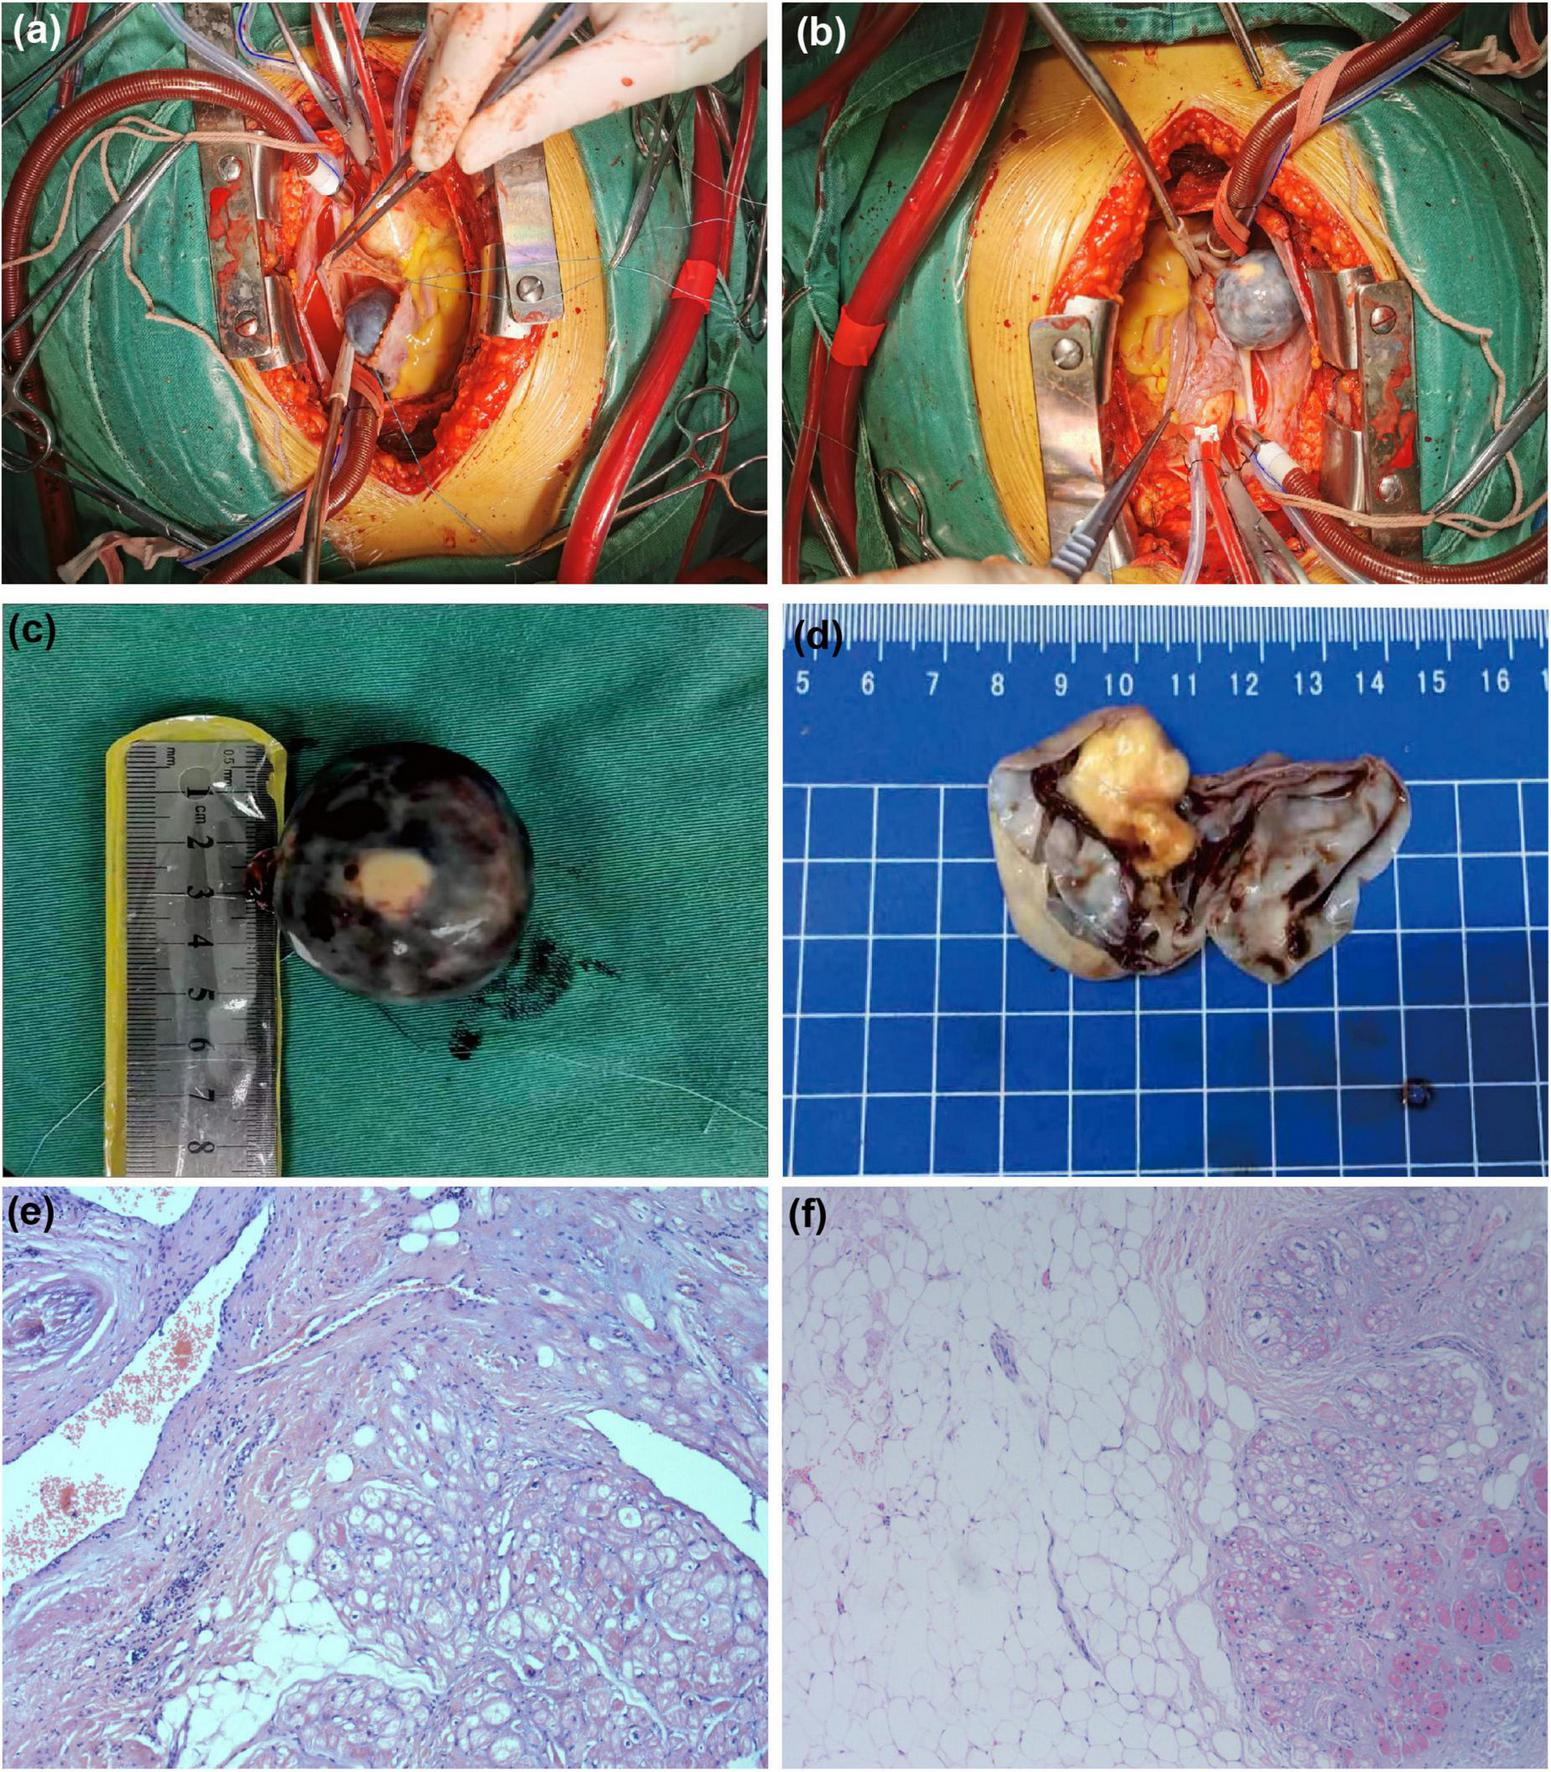

Surgical and pathological findings

After the above examinations had been completed, the patient underwent elective right atrial tumor resection. Intraoperative examination revealed moderate cardiac enlargement, and a spherical mass with a size of about 3.0 cm × 4.0 cm could be seen in the right atrium, the tumor was connected to the right atrial side of the right atrial septum under the oval fossa with a small tumor pedicle (Figures 4A, B). Subsequent dissection thereof resulted in the outflow of a large volume of dark red liquid, after which a solid yellow-white tumor with a rough texture was observed attached to one side of the cyst wall (Figures 4C, D). Postoperative pathological examination via light microscopy revealed large sheets of mature adipocytes interspersed between the myocardium, leading to the diagnosis of a cardiac lipoma (Figures 4E, F).

FIGURE 4

www.frontiersin.org

Figure 4. Surgical and pathological results. The tumor was spherical mass (A) and that was connected to the right atrial side of the right atrial septum under the oval fossa with a small tumor pedicle (B). (C) The ex vivo tumor was black spherical. (D) It can be observed that the yellowish white solid tumor with rough texture is attached to one side of the cyst wall after dissecting the tumor. (E,F) Stained with hematoxylin and eosin (H&E) at 10 magnification: the tumor comprised mature adipocytes with entrapped myocardial cells.